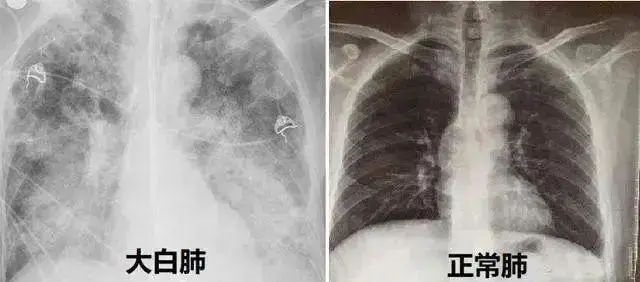

正常的胸片肺呈黑色。如果肺里有炎症,痰液充斥肺泡后,胸片呈白色,这就大白肺!

并不是只要肺部出现了炎症就都叫白肺,一般来讲肺部炎症较重、渗出液较多,白色的影像区域面积达到70%—80%时,在临床上把它称为白肺。出现白肺之后,患者就会出现低氧血症或者是呼吸窘迫。目前主要涉及高龄的合并严重基础疾病的患者,但占比非常低。